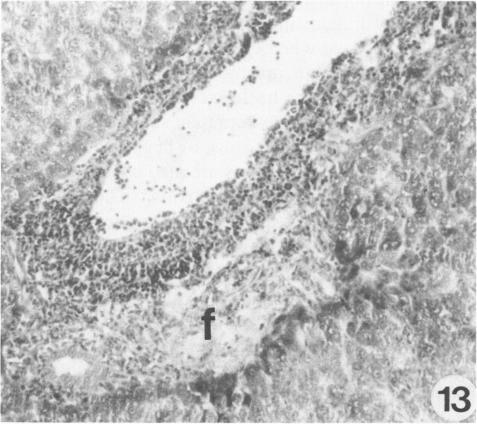

The pathogenesis of experimentally induced cecal amebiasis in gerbils (Meriones unguiculatus) was studied from 5 to 60 days after inoculation. Ulcerative lesions were noted 10 to 60 days after inoculation. The sequential development of lesions was asynchronous and progressed from destruction of the interglandular epithelium and of glandular crypt elements to loss of mucosa and formation of granulomatous lesions in the submucosa involving the muscularis mucosae. Pathologic changes in the liver correlated with the formation of ulcerative cecal lesions. Subacute hepatic changes showed lymphocytic portal infiltrate, Kupffer cell hyperplasia, multinucleated giant cells, granuloma formation, and sinusoidal mononuclear and granulocytic infiltrates. Metastatic amebic liver abscesses occurred as early as 10 days after inoculation, and small abscesses were found in the portal areas of the right liver lobe. The sequential development and pathologic manifestation of the infection and the usefulness of the gerbil for the study of human intestinal amebiasis are discussed.

在接种后5至60天,对沙土鼠(长爪沙鼠)实验性诱导盲肠阿米巴病的发病机制进行了研究。接种后10至60天观察到溃疡性病变。病变的连续发展是异步的,从腺间上皮和腺隐窝成分的破坏发展到黏膜丧失,并在涉及黏膜肌层的黏膜下层形成肉芽肿性病变。肝脏的病理变化与盲肠溃疡性病变的形成相关。亚急性肝脏变化表现为淋巴细胞门静脉浸润、库普弗细胞增生、多核巨细胞、肉芽肿形成以及窦状隙单核细胞和粒细胞浸润。转移性阿米巴肝脓肿最早在接种后10天出现,在右肝叶门静脉区域发现小脓肿。讨论了感染的连续发展和病理表现以及沙土鼠在人类肠道阿米巴病研究中的用途。